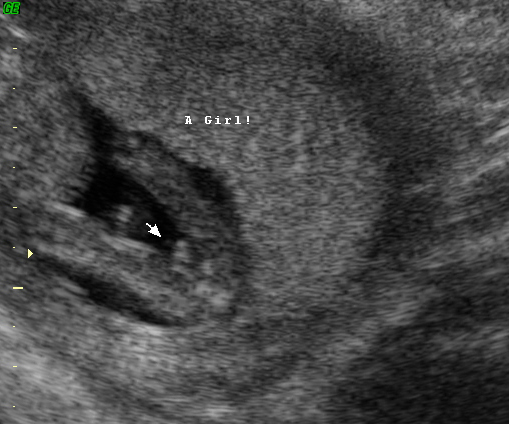

Any guesses.... Us tech said she guesses girl

first photo is showing the cord, from second photo I would say girl! :)

well girls...it's still a little bit early (13w6d), but had to go back in for another u/s and got this: 100% girl from the tech this time (even though it's still early). Anyone still leaning boy? :)

Attachment 1902